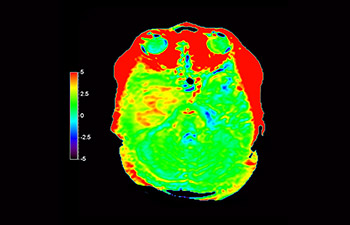

In een samenleving waarin veel neurologische aandoeningen voorkomen, streeft Philips naar een superieure duidelijkheid op het gebied van diagnoses en behandelingsbegeleiding voor alle patiënten. Hoewel MR vandaag de dag de gouden standaard is in neuro-oncologische beeldvorming, is er nog ruimte voor verbetering van de nauwkeurigheid bij het beoordelen van tumoren en follow-ups. 3D APT (Amide Proton Transfer) is een unieke, contrastvrije MR-beeldvormingsmethode voor de hersenen als antwoord op de vraag naar betrouwbaardere diagnostiek in de neuro-oncologie. 3D APT maakt gebruik van de aanwezigheid van endogene celeiwitten voor het produceren van een MR-signaal dat direct correleert met celproliferatie, een marker voor tumoractiviteit. 3D APT kan getrainde medische professionals ondersteunen bij het maken van onderscheid tussen laaggradige en hooggradige gliomen en tussen de ontwikkeling van de tumor en het effect van de behandeling1.

met 3D APT